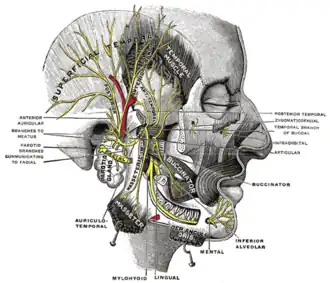

Muscles of mastication

Innervation

Unlike most of the other facial muscles, which are innervated by the facial nerve (or CN VII), the muscles of mastication are innervated by the trigeminal nerve (or CN V). More specifically, they are innervated by the mandibular branch, or V3. The mandibular nerve is both sensory and motor.